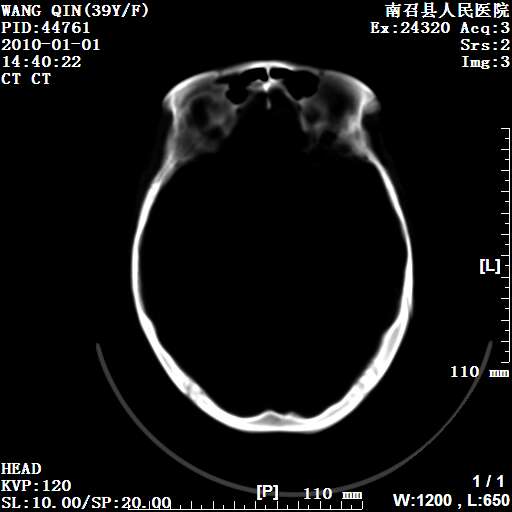

以下是引用随光逐影在2010-1-22 9:03:00的发言:[br]考虑左侧中颅窝(蝶骨翼区)脑膜瘤侵犯蝶骨翼并突入左侧眼眶。

以下是引用水过无痕在2010-1-22 14:55:00的发言:[br]一、定位:颅外占位;二、定性:恶性可能性大;三、组织来源:来源于左侧眼外直肌或其他部位;考虑为:横纹肌肉瘤>转移瘤>脑膜瘤.